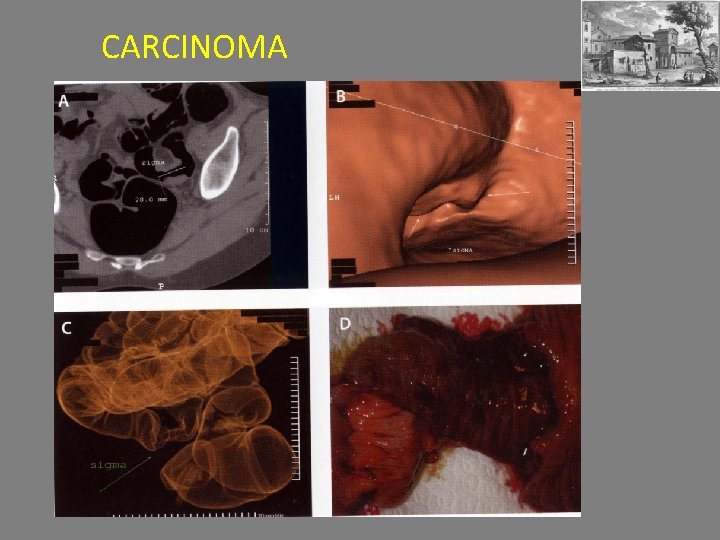

CARCINOMA